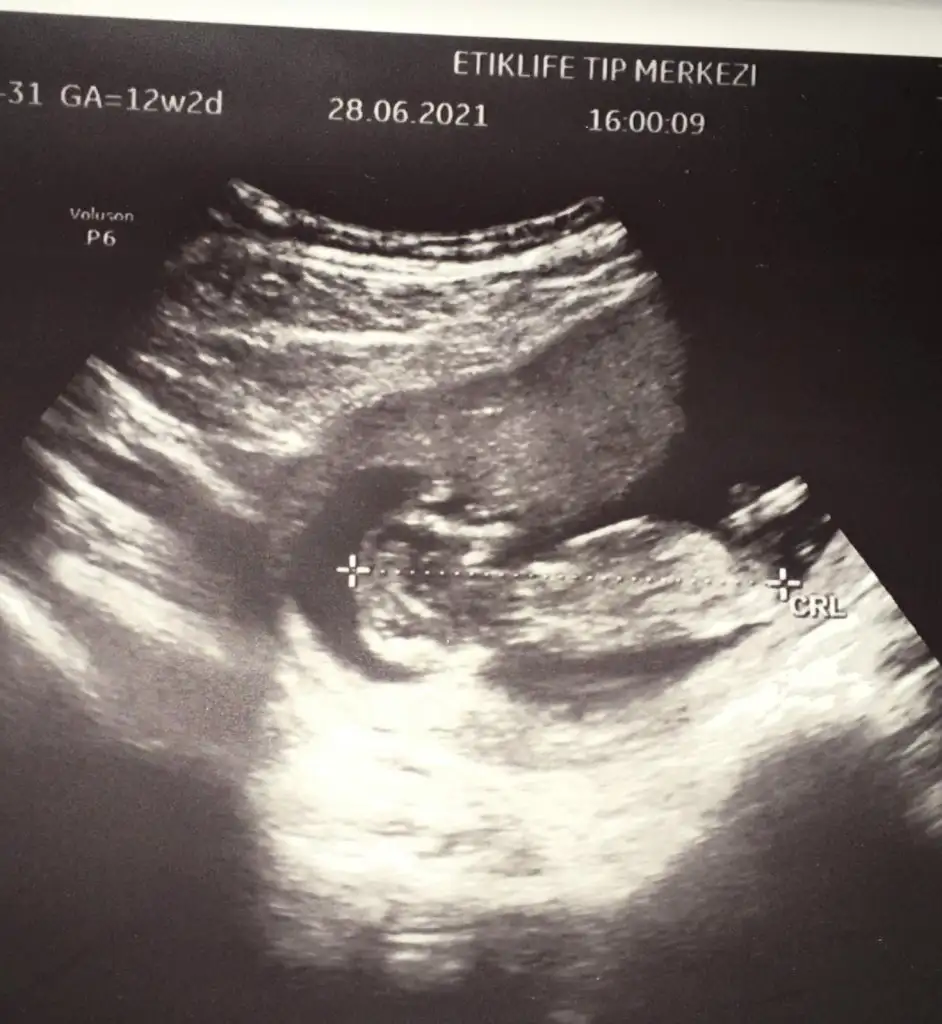

T tulperde Benim de ultrason görüntüm

Kıza mı benziyor erkeğe mi :))

WhatsApp Image 2021-06-28 at 20.26.41.webp